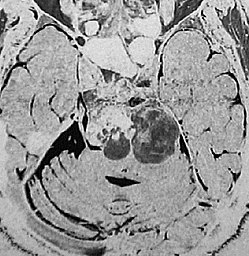

左動眼神経麻痺が急速に進行した例です。斜台から左海綿静脈洞,錐体骨尖を侵す頭蓋底軟骨肉腫です。左内頚動脈は腫瘍に取り囲まれています。

CTでは腫瘍実質部分が増強されます。不規則な骨破壊像・浸食像が特徴的です。

T2強調画像で高信号となるのは脊索腫と同様です。斜台後方の硬膜を破って前橋槽に伸展しています。これも脊索腫と同じような伸展浸潤形態と言えます。

グレード2の軟骨肉腫でした。軟骨肉腫は軟らかい腫瘍です。もちろん頭蓋底骨に浸潤しているので全摘出は無理ですが,大部分を摘出して術後に放射線治療をするのが標準的な治療です。ガンマ線による放射線治療でもコントロールできることは多いでしょう。逆に,重粒子線(炭素線)などの治療は侵襲的過ぎます。

骨軟骨腫 osteochondroma の悪性化例:secondary chondrosarcoma

骨軟骨腫が若い時からあって壮年になってから悪性化した軟骨肉腫です。20代のときに右外転神経麻痺が生じて20年以上そのまま経過しました。左のCTでは頭蓋骨の真ん中の斜台というところに異常な骨があって,良性の骨軟骨腫のように見えます。でも右側のMRIでは脳幹部に深く食い込む柔らかい腫瘍の部分が写っていてこれは軟骨肉腫を疑う像です。手術摘出と術後の放射線治療をしました。